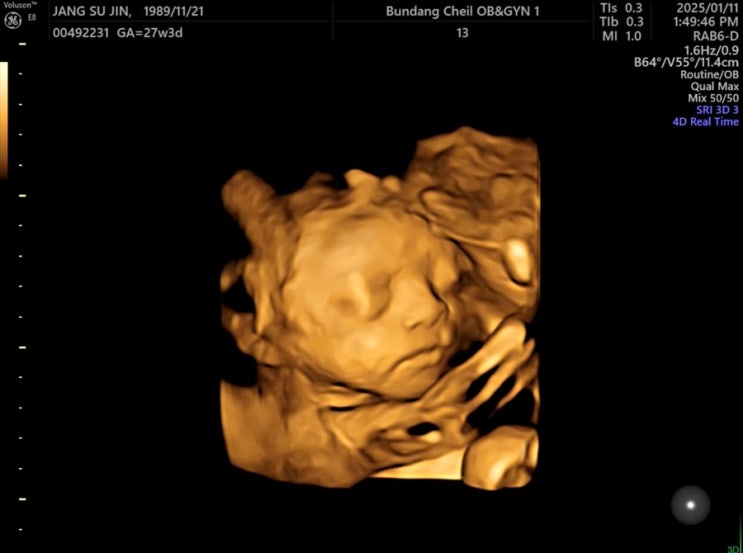

임신 27주차 - 일상, 27주 입체초음파, 아기얼굴, 코엑스 2025 맘스홀릭베이비페어, 애슐리퀸즈, 휴직 스타또

고구미!! 맛있는데 먹을때마다 코코 눈치봐야함ㅋㅋ 요염해라~ 병원가는날! 코코이찌방야 가서 카레 푸파!!...